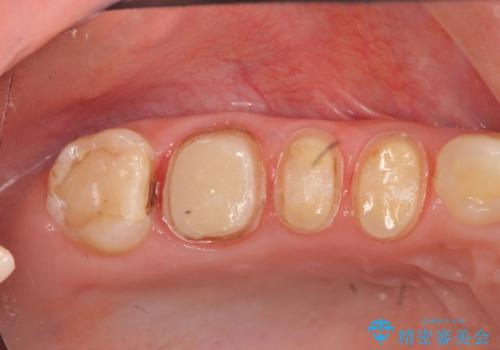

- 歯の疼きや違和感、虫歯の治療を希望され来院されました。

銀歯周囲の虫歯再発や、歯ぐきよりも深い虫歯、根尖性歯周炎と言った複合的な問題を、

歯周外科、精密根管治療、セラミック治療を行い、妥協のないセラミック治療を計画します。